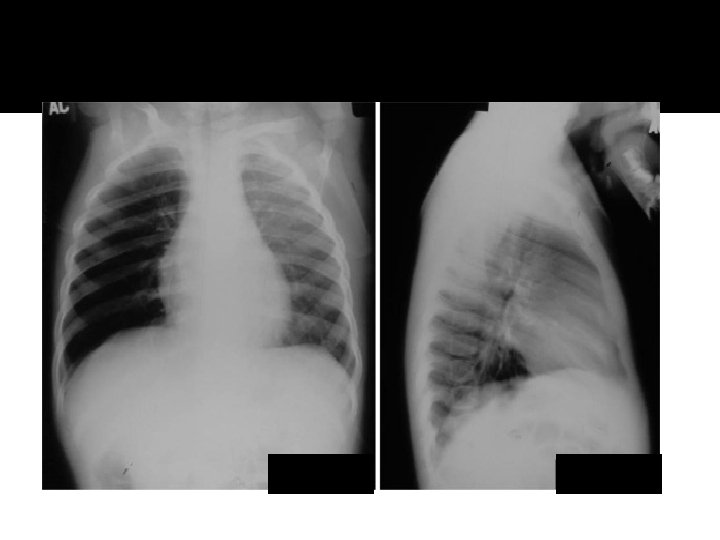

Atelectasis RML

Atelecasis RML